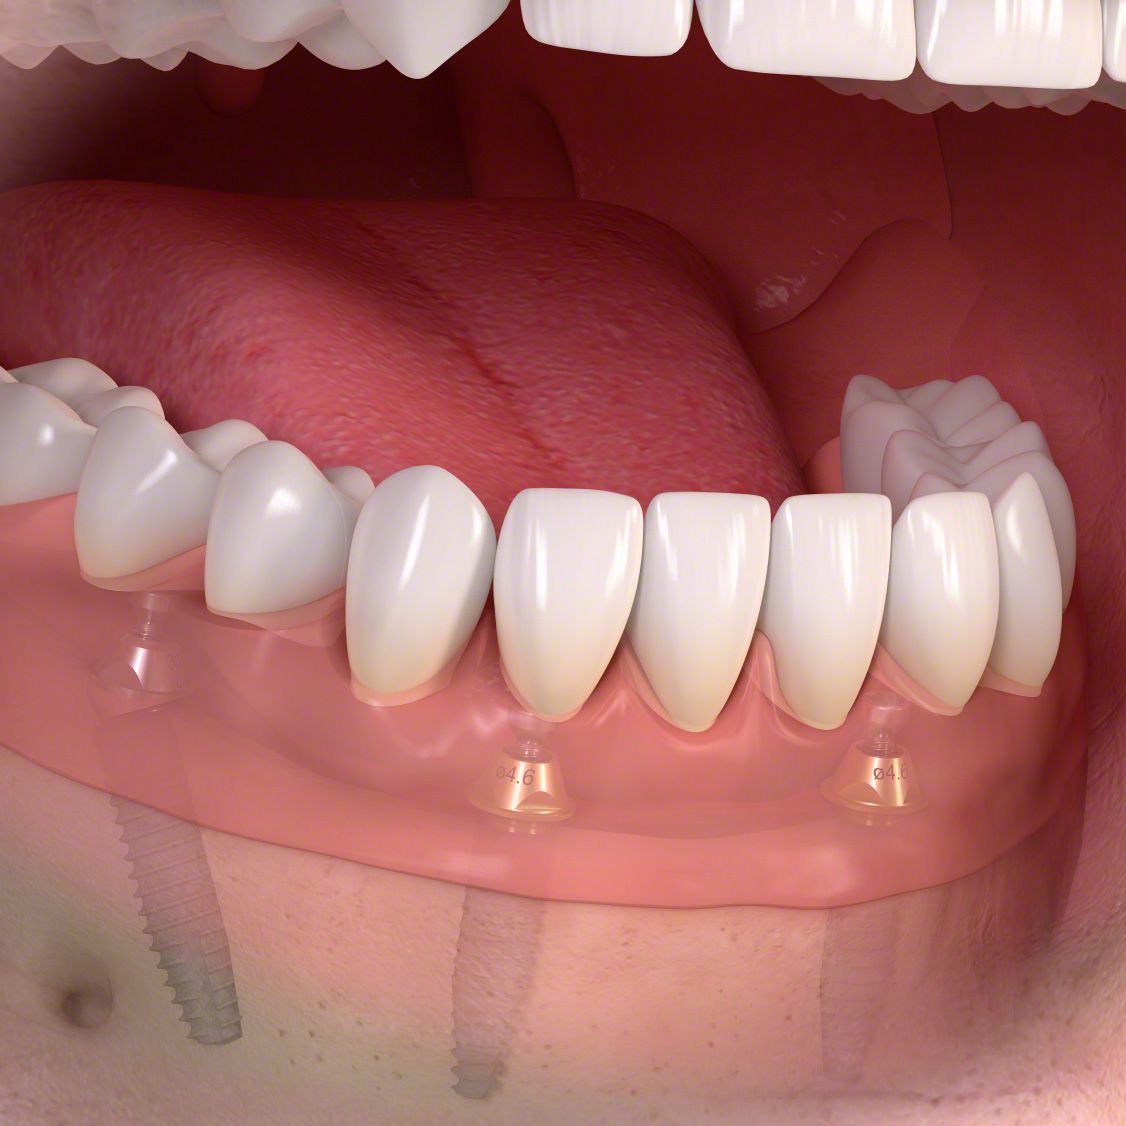

Jeder eigene Zahn ist wertvoll! Wie wertvoll, merkt man erst, wenn er ersetzt werden muss. Im Laufe des Lebens ist das leider oft der Fall. Doch dank Implantaten können wir nicht nur Zahnlücken schließen, sondern sogar kompletten Zahnersatz fest im Mund verankern. Da wackelt nichts mehr!

Die entstandene Lücke kann mit einer künstlichen Zahnwurzel, d.h. mit einem Implantat geschlossen werden. Implantate, meist aus Titan oder Keramik, werden dabei in einem kleinen chirurgischen Eingriff in den Kieferknochen eingesetzt. Nach dem Einheilen tragen sie später den eigentlichen Zahnersatz (Kronen, Brücken, Prothesen).

Implantate sind eine langlebige, festsitzende und komfortable Lösung und tragen damit zu mehr Wohlbefinden und Lebensqualität bei. Allerdings brauchen Sie besondere Aufmerksamkeit und Pflege: mit regelmäßiger Prophylaxe – alle 3 bis 4 Monate – werden Sie über viele Jahre Freude an Ihren neuen, festsitzenden Zähnen haben.